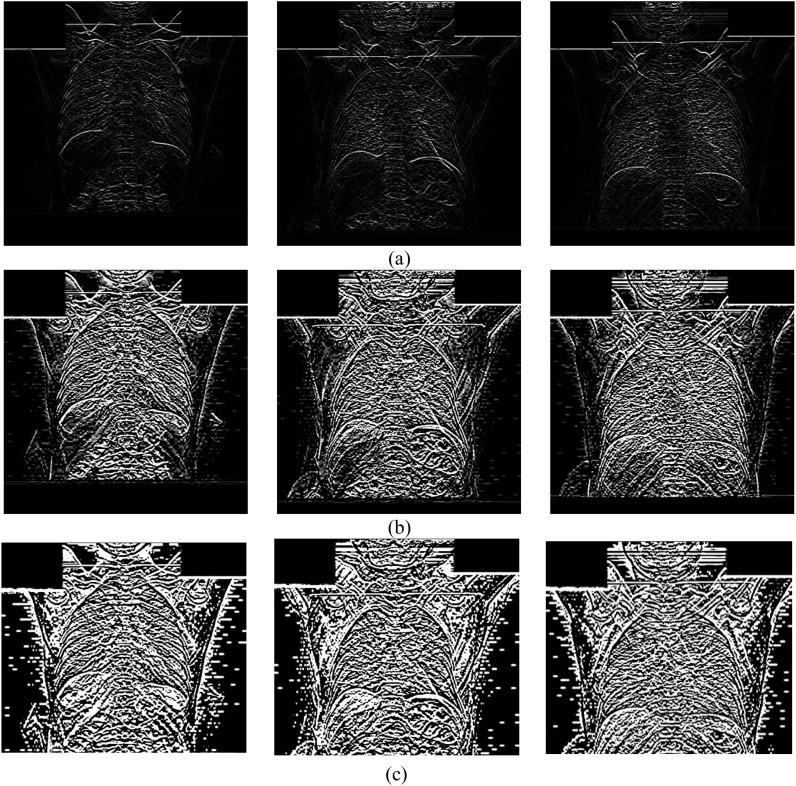

The coronavirus (COVID-19) is currently the most common contagious disease which is prevalent all over the world. The main challenge of this disease is the primary diagnosis to prevent secondary infections and its spread from one person to another. Therefore, it is essential to use an automatic diagnosis system along with clinical procedures for the rapid diagnosis of COVID-19 to prevent its spread. Artificial intelligence techniques using computed tomography (CT) images of the lungs and chest radiography have the potential to obtain high diagnostic performance for Covid-19 diagnosis. In this study, a fusion of convolutional neural network (CNN), support vector machine (SVM), and Sobel filter is proposed to detect COVID-19 using X-ray images. A new X-ray image dataset was collected and subjected to high pass filter using a Sobel filter to obtain the edges of the images. Then these images are fed to CNN deep learning model followed by SVM classifier with ten-fold cross validation strategy. This method is designed so that it can learn with not many data. Our results show that the proposed CNN-SVM with Sobel filter (CNN-SVM + Sobel) achieved the highest classification accuracy, sensitivity and specificity of 99.02%, 100% and 95.23%, respectively in automated detection of COVID-19. It showed that using Sobel filter can improve the performance of CNN. Unlike most of the other researches, this method does not use a pre-trained network. We have also validated our developed model using public databases and obtained the highest performance. Hence, our developed model is ready for clinical application.

冠状病毒(COVID-19)是目前全球最常见的传染病。这种疾病的主要挑战在于进行初步诊断以预防继发感染及其在人与人之间的传播。因此,使用自动诊断系统并结合临床程序对COVID-19进行快速诊断以防止其传播至关重要。利用肺部计算机断层扫描(CT)图像和胸部X光片的人工智能技术有潜力在COVID-19诊断中获得较高的诊断性能。在本研究中,提出了一种卷积神经网络(CNN)、支持向量机(SVM)和索贝尔滤波器的融合方法,用于使用X射线图像检测COVID-19。收集了一个新的X射线图像数据集,并使用索贝尔滤波器对其进行高通滤波以获取图像边缘。然后将这些图像输入到CNN深度学习模型,接着使用具有十折交叉验证策略的SVM分类器。该方法的设计使其能够在数据量不多的情况下进行学习。我们的结果表明,所提出的带有索贝尔滤波器的CNN-SVM(CNN-SVM + 索贝尔)在COVID-19自动检测中分别达到了最高的分类准确率、灵敏度和特异性,分别为99.02%、100%和95.23%。结果表明,使用索贝尔滤波器可以提高CNN的性能。与大多数其他研究不同,该方法不使用预训练网络。我们还使用公共数据库对我们开发的模型进行了验证,并获得了最高性能。因此,我们开发的模型已准备好用于临床应用。